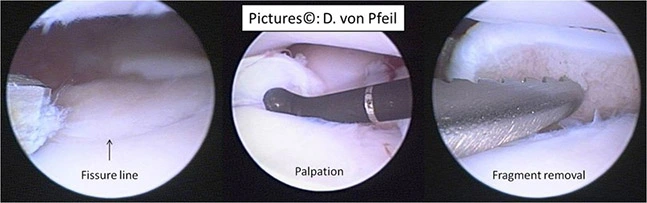

Arthroskopische Bilder eines fragmentierten Koronoids – ein Knochenstück im Ellenbogengelenk. Links: Fissur (Pfeil); Mitte: Palpation; rechts: Fragmententfernung